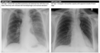

**Heart failure** Alveolar batwing shadowing Kerley B lines Cardiomegaly Upper lobe Diversion Pleural Effusion

Causes of white out on CXR

Upper zone opacification RUL = limited by horizontal fissure LUL = indistinct heart border if lingula

Middle lobe opacification Indistinct heart border

Lower lobe opacification Indistinct diaphragm border